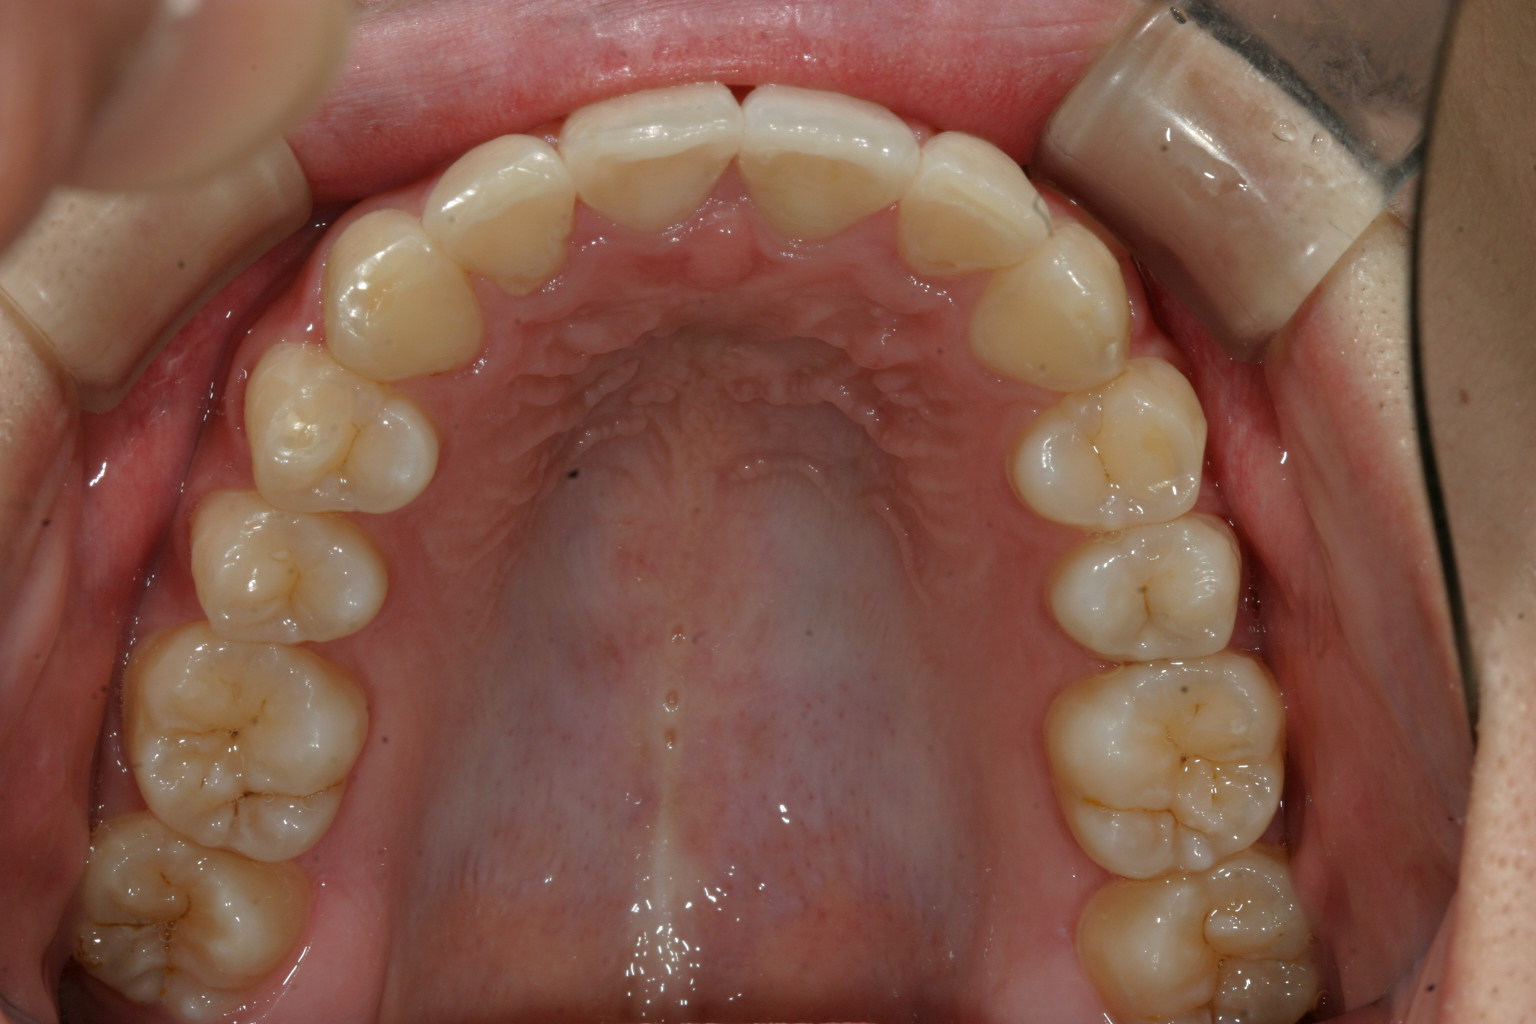

歯列がV字型になってます。

綺麗なアーチにしました。

この様に上下の歯列がV字になることにより口ボゴが生じてます。犬歯と犬歯の間が狭い為に前歯4本が並ぶことが出来ない為仕方なくV字の歯列になった珍しい症例です。